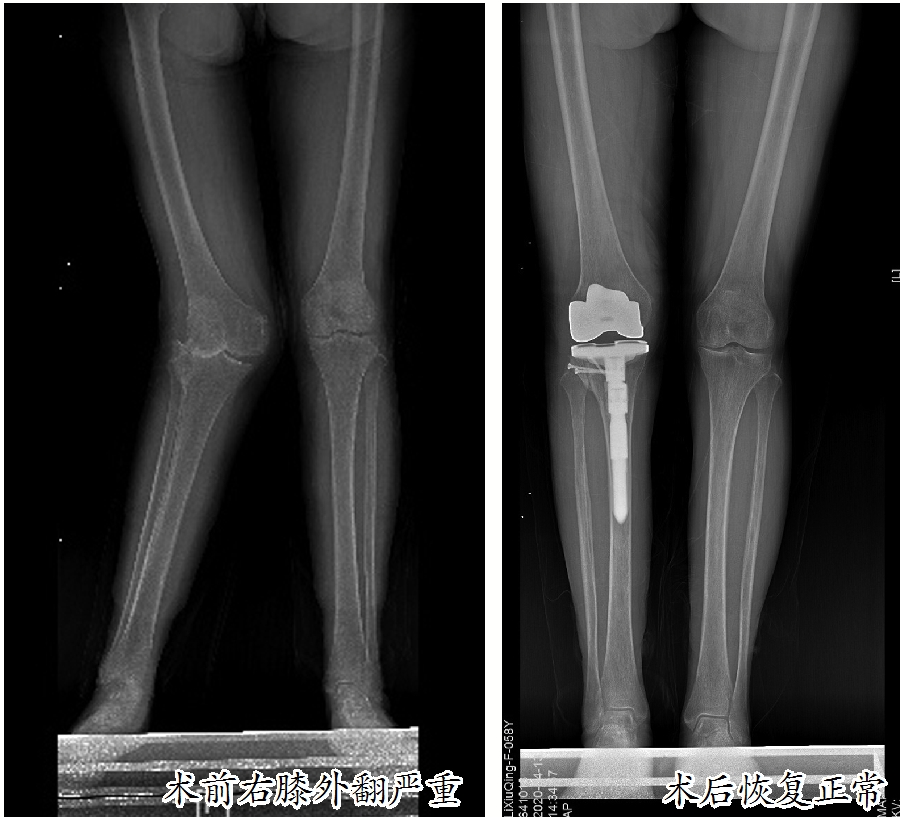

这名患者名叫李素严(化名),患有类风湿性关节炎多年,近半年感觉双侧膝关节疼痛严重,影响了日常生活,来到市人民医院骨科中心关节外科、运动医学科就诊。入院后,经过双侧膝关节X线检查发现:双膝关节存在不同程度的退行性变,其中右膝关节退化严重,重度外翻畸形,外翻角度超过30度,属于重度膝外翻,已经到了必须治疗的地步。

膝外翻又称为“X型腿”“K型腿”或“碰膝症”。在医学上,正常人的膝关节有5至7度的外翻角,如果超过此角度就是病态。膝关节向外侧倾斜10至15度为轻度外翻,超过15至30度为中度外翻,外翻角大于30度为重度外翻。

经过严密的术前准备,张新虎教授主刀对李素严实施了手术。他凭借多年的手术经验以及对膝关节结构的熟悉,在未伤及血管、神经的情况下精准完成了胫骨、股骨的截骨以及软组织松解,在检查下肢力线、膝关节屈度和伸直状态的稳定性、髌骨的运动轨迹后安装了假体。由于术前方案准备完善,术中可能出现的情况都基本得到了解决。